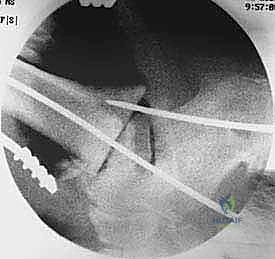

5. التثبيت بالبراغي القفلية (Locking Screws)

لضمان عدم تحرك المسمار أو دوران العظام حوله، يتم تثبيت المسمار ببراغي عرضية تخترق العظام والمسمار معاً من الأعلى (في الساق) ومن الأسفل (في الكعب والكاحل). يتم استخدام جهاز التصوير الإشعاعي (C-arm) داخل غرفة العمليات للتأكد من الموضع المثالي لكل مسمار.